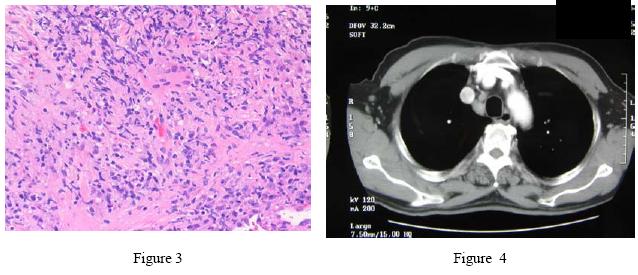

The sputum for AFB smears was negative on two occasions. Fibro-optic bronchoscopy (FOB) was performed on 28/6/2005; there was no endobronchial lesion and bronchial aspirate for AFB smear & culture were negative. Transbronchial biopsy from apical segment of RLL showed infiltration of lymphocytes, plasma cells and multinucleated giant cells, non-caseating granulomatous inflammation and fibrosis. The PCR for MTB DNA was however negative (Figure 3). Out-patient CT thorax and abdomen on 14/7/2005 confirmed no other mass lesion in both lungs. The abnormal findings included multiple enlarged lymph nodes in the pre-carinal, right paratracheal and bilateral hilar regions as well as striated enhancement pattern in both kidneys (Figure 4). He was referred to our respiratory clinic for follow up by our geriatric colleague but he defaulted again.